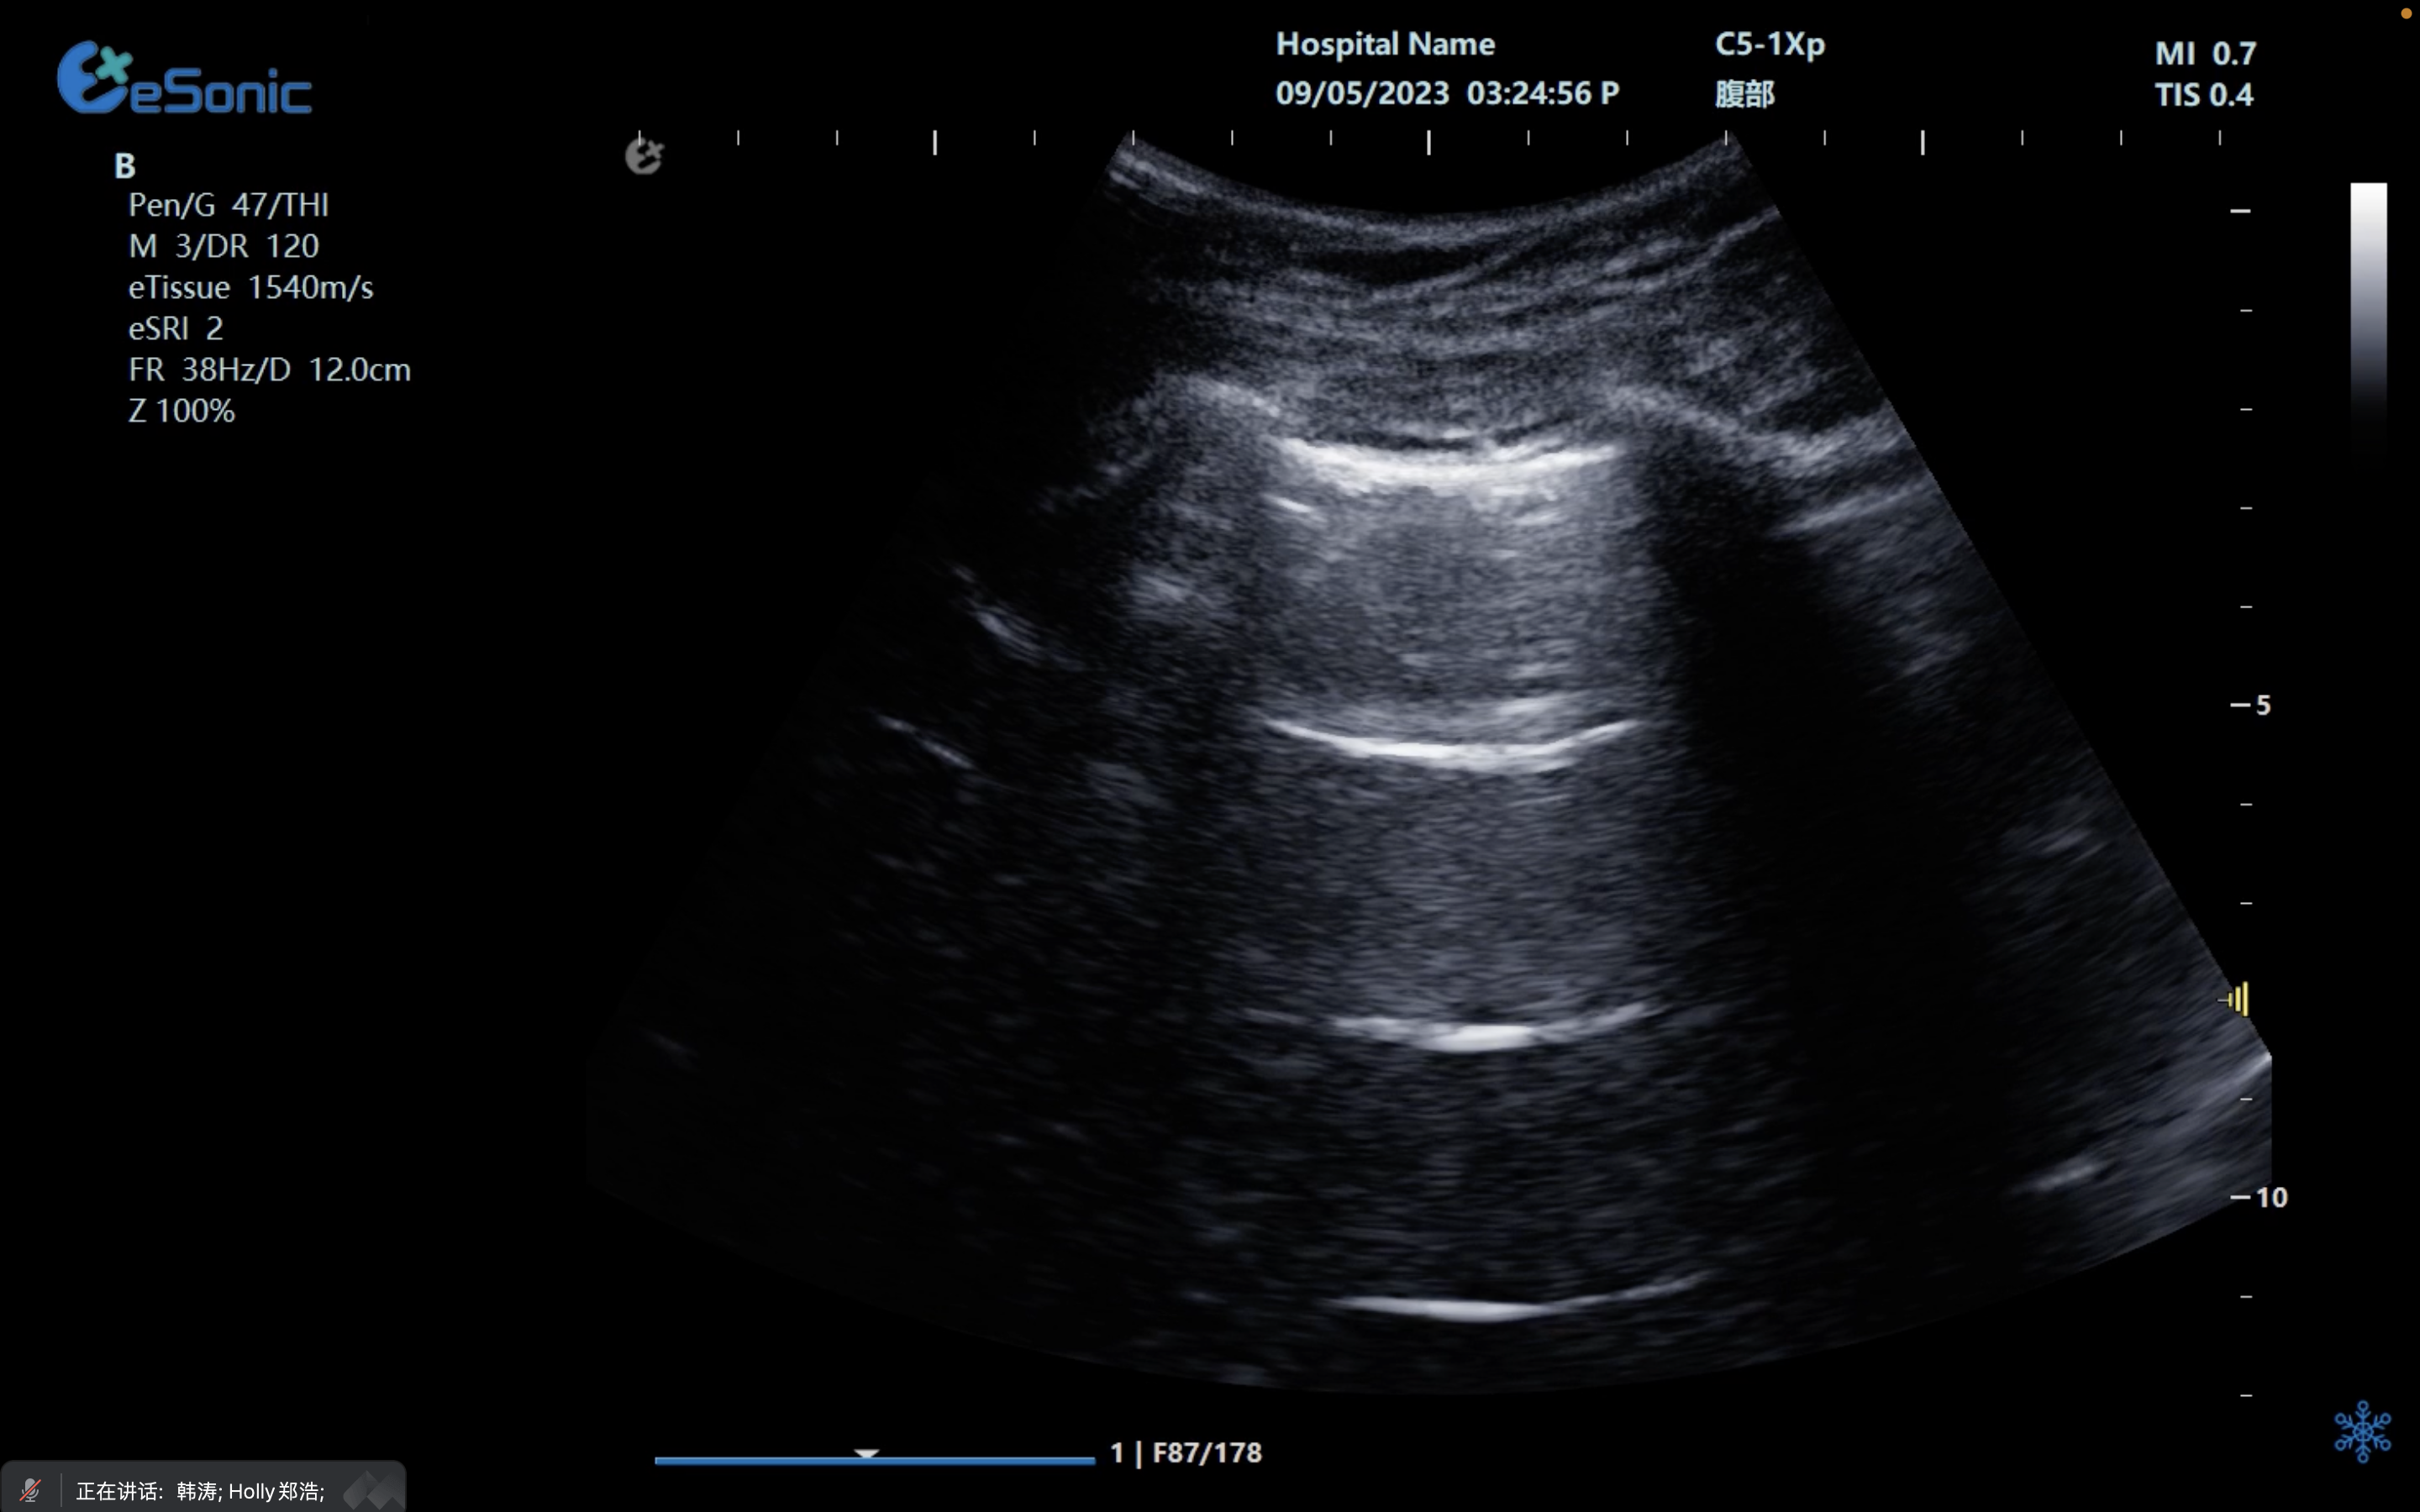

剑突下四腔心切面

image.png

扫查方法:探头置于剑突下,声束指向左肩,稍向上倾斜30°,接近心脏冠状切面

超声声像图:图像近场扇尖处可见肝实质反射,此切面可观察左心房、左心室、右心房、右心室、房间隔、室间隔、二尖瓣、三尖瓣等结构。